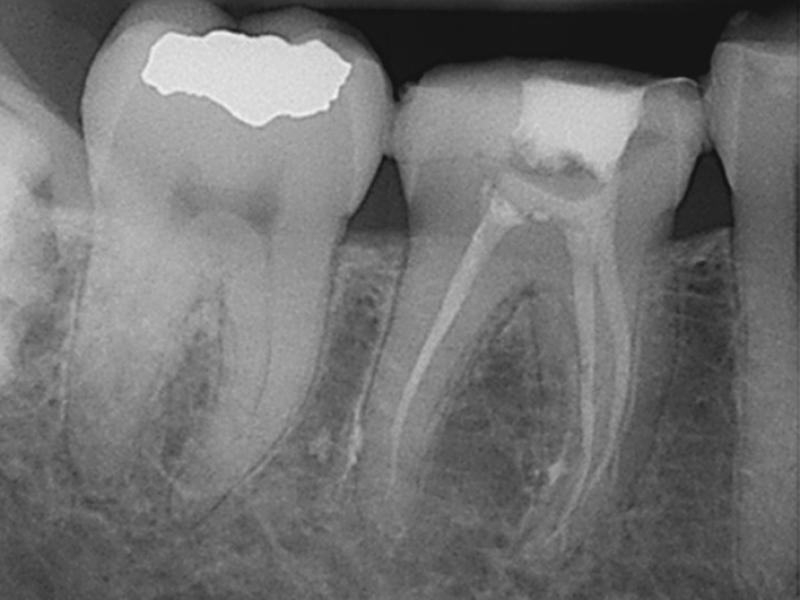

Middle Mesials in MN Molars

Middle Mesials in MN Molars with 10 Months Healing Evidence

Nestor Cohenca, DDS, FIADT

View Case Images